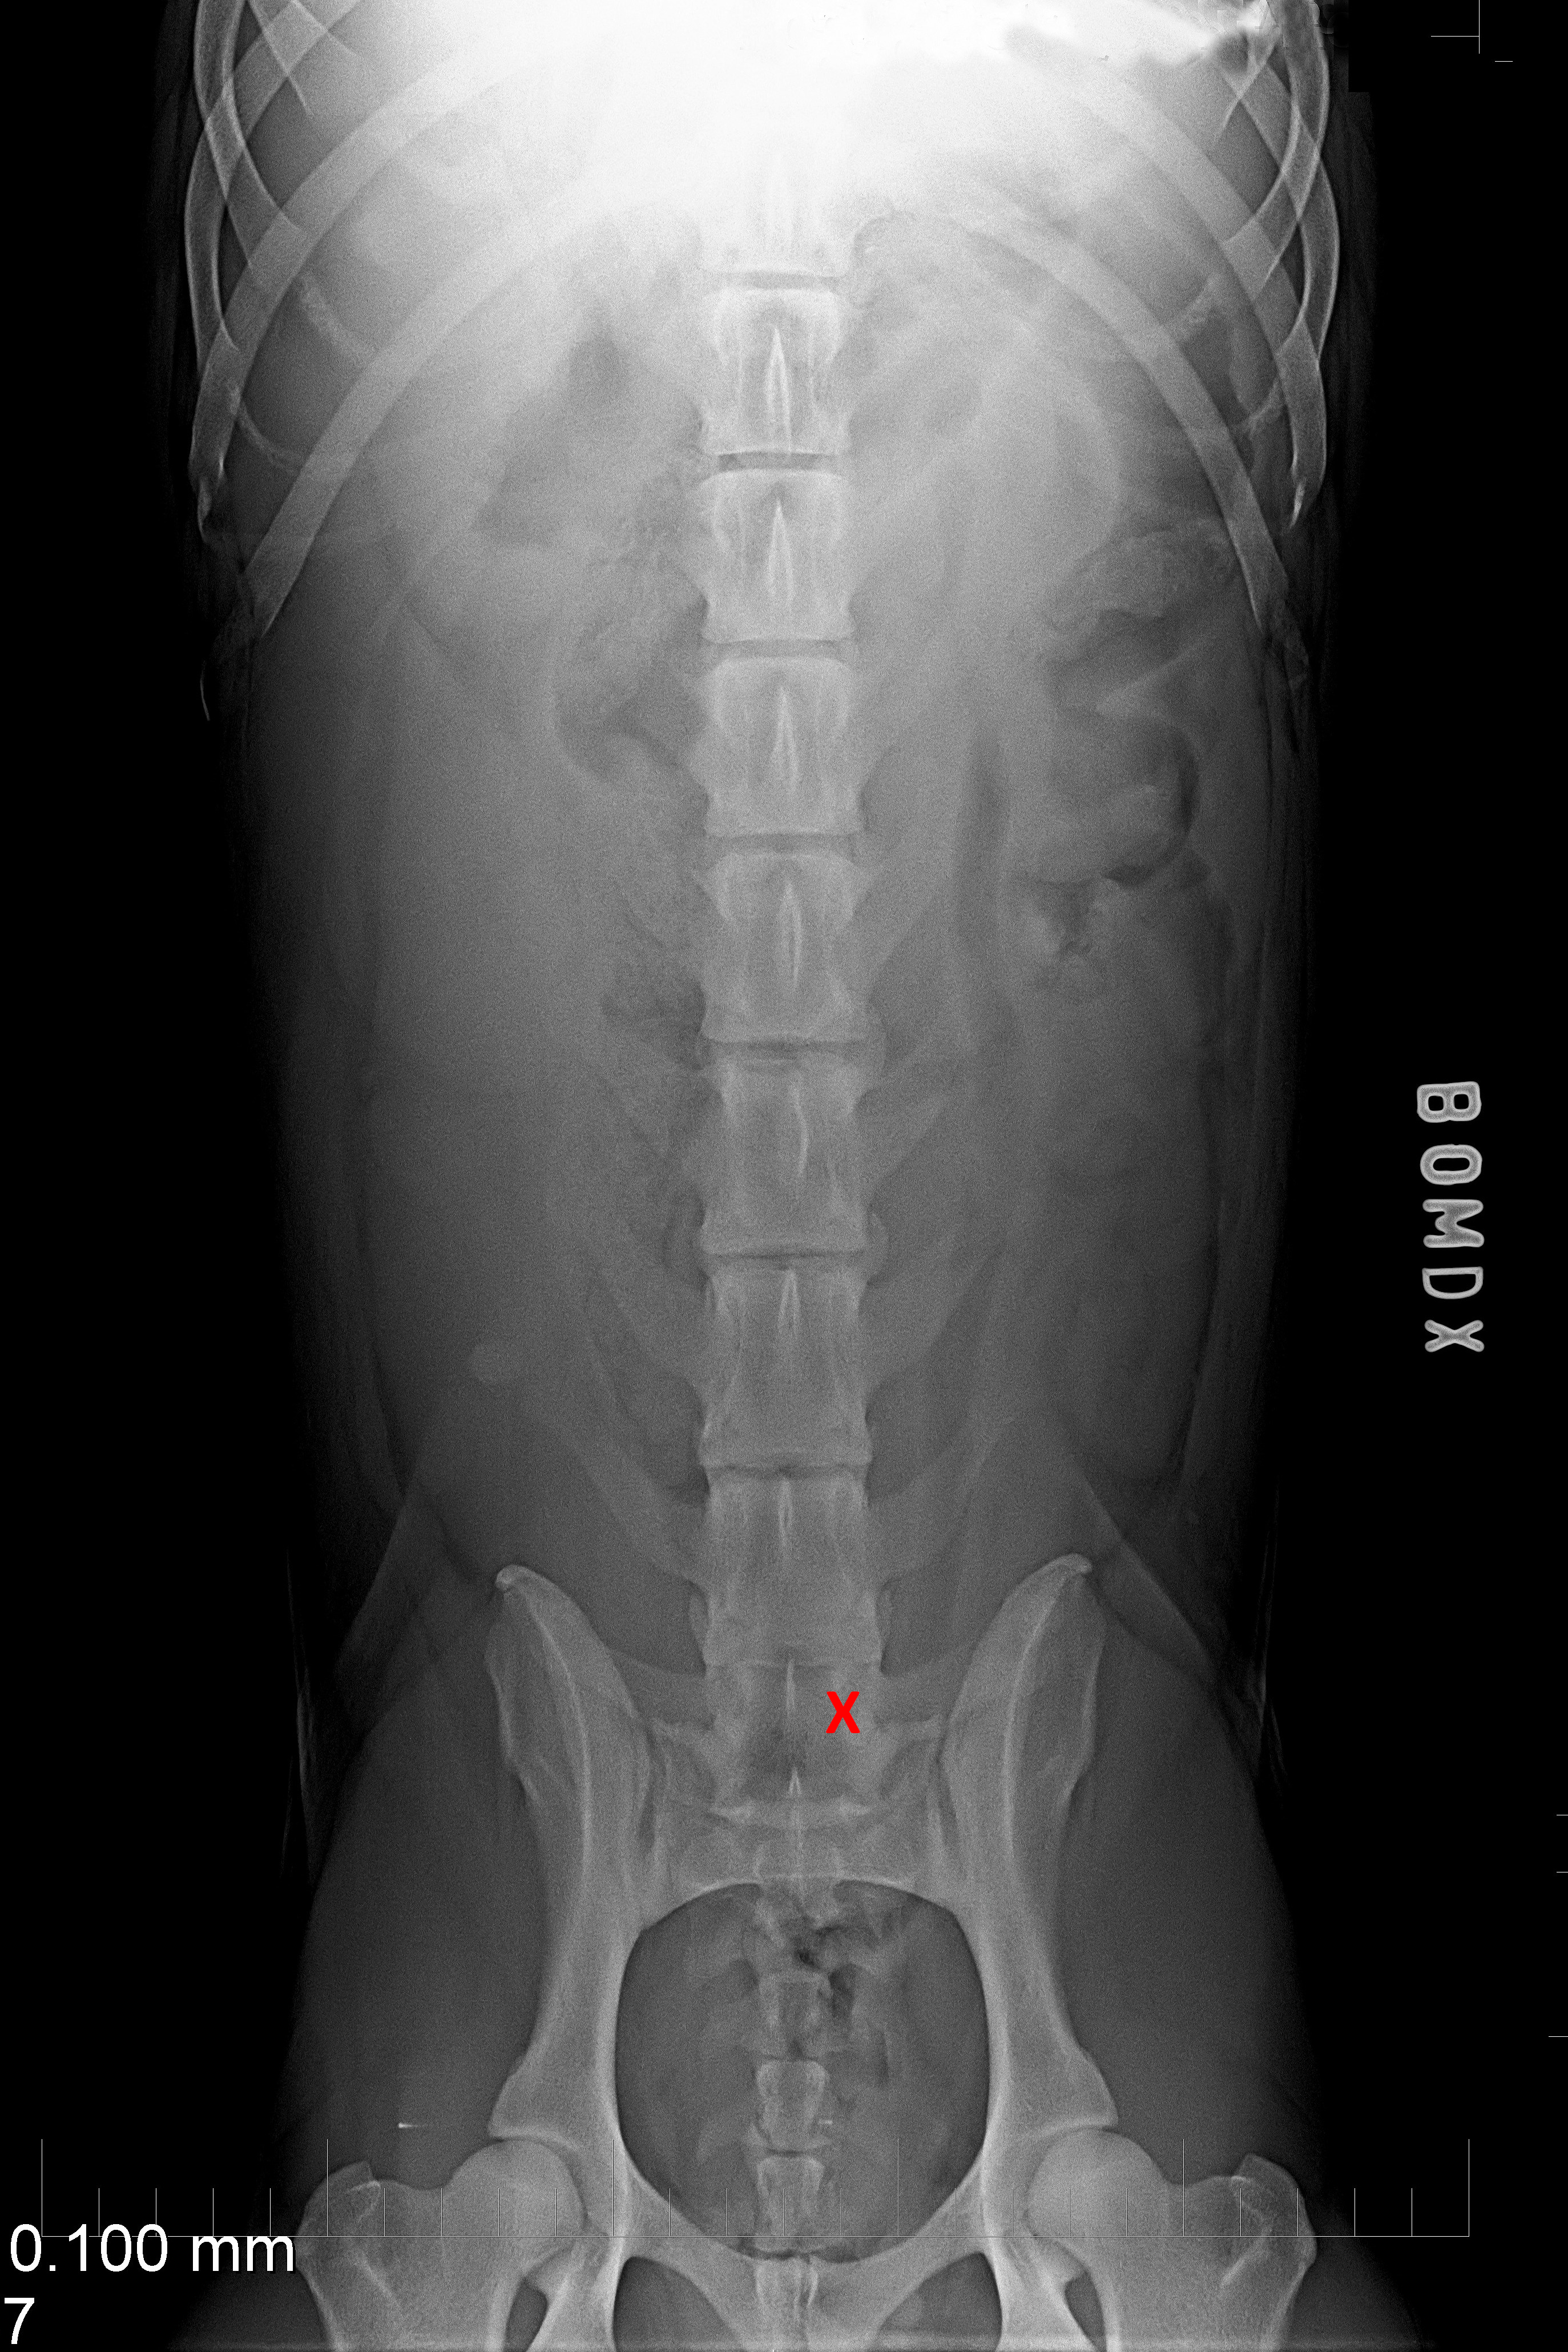

(3) 7 měsíců VD 1

(3) typ 3 po korekci polohy pánve

(4) 7 měsíců VD 2

(4) typ 3 po korekci polohy pánve 2

(5) typ 3 páteř VD